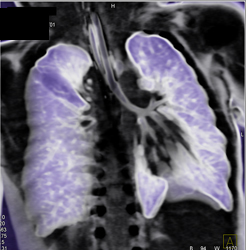

Scv Syndrome With Collaterals Through and Into IVC